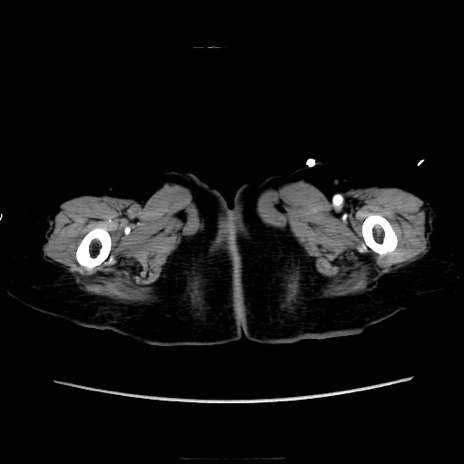

症例40(横断像)

横断像